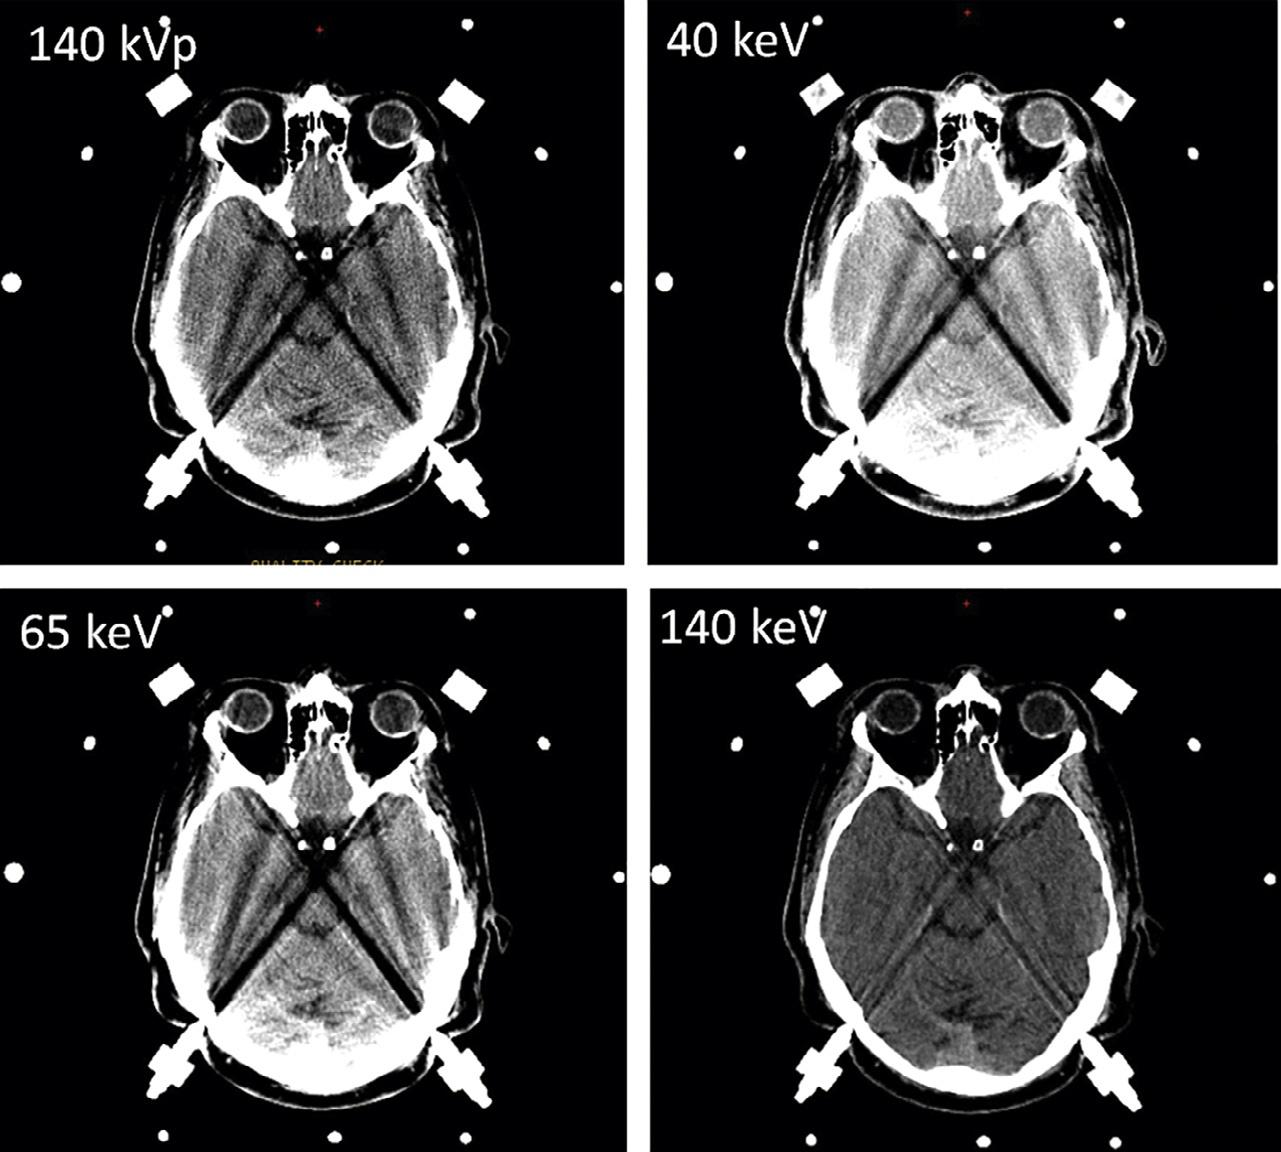

AdvancesinCTneuroimaginghaveparalleled advancesincomputerprocessingspeedandinefficiency ofimagereconstructionalgorithms.Mostrecently,iterativereconstructiontechniques – thefirstgenuinely novelCTimage-processingdevelopmentsinceHounsfield’sfilteredbackprojectionmethodology(forwhich hewasawardedtheNobelPrizein1979) – havemade possiblehighspatialresolution,reducednoise,very lowradiationdoseCTscanning(Rapalinoetal.,2012). Theimprovedscanningspeed, z-directioncoverage,spatialresolution,contrastresolution,andlowradiation dosecapabilityofpresent-dayCTscannershavealso facilitateddual-energyimaging,which – forthefirst time,likeMRI – hasallowedtissue-specificcharacterizationofintracranialpathology,includingdedicatedCT imagingthatcanreliablydistinguishcalcium,iodine,fat, water,andhemorrhage(Guptaetal.,2010).Virtual monochromaticdual-energyCTimagesalsohavethe potentialtohelpreducetheposteriorfossabeamhardeningartifactcausedbydenseboneattheskullbase (Pomerantzetal.,2013).

Fig.1.17. Dual-energyvirtualmonochromaticimagesofacontrast-enhancedbrainatthreedifferentenergylevels:50keV(top right),65keV(bottomleft),and130keV(bottomright).Withdual-energycomputedtomography,virtualmonochromaticreconstructionatlowerkeVlevelsimprovesintravascularenhancementandcontrast-to-noiseratioastheX-rayphotonenergymoves closertothe k-edgeofiodine(33.2keV).Ascanbeseen,theattenuationwiththevesseljumpsfrom169HUto1156HUwhenwe movefrom130keVto50keV.Withthischange,thebrainparenchymaonlygoesfrom18HUto45HU.Thisfactcanbeusedto drasticallycutdowntheamountofcontrastthatisadministered,withobviousbenefitsintermsofrenalhealth.